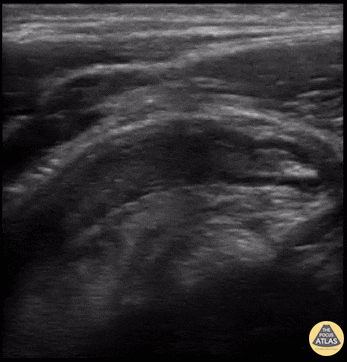

Bowel-GI - Appendicitis (Long Axis)

18 y/o with severe acute onset RLQ abdominal pain, associated with vomiting. Temp 100.8 with guarding over RLQ. POCUS performed and revealed appendicitis. 8mm dilated, non-compressible, aperistaltic appendix with an appendicolith present (hyperechoic structure in blind end of appendix) surrounded by free fluid. Tender directly over the appendix. The psoas muscle can be seen on the right side, and bowel can be seen to the left. Drs. Bryan Jarret, Sathya Subramaniam - Kings County/SUNY Downstate